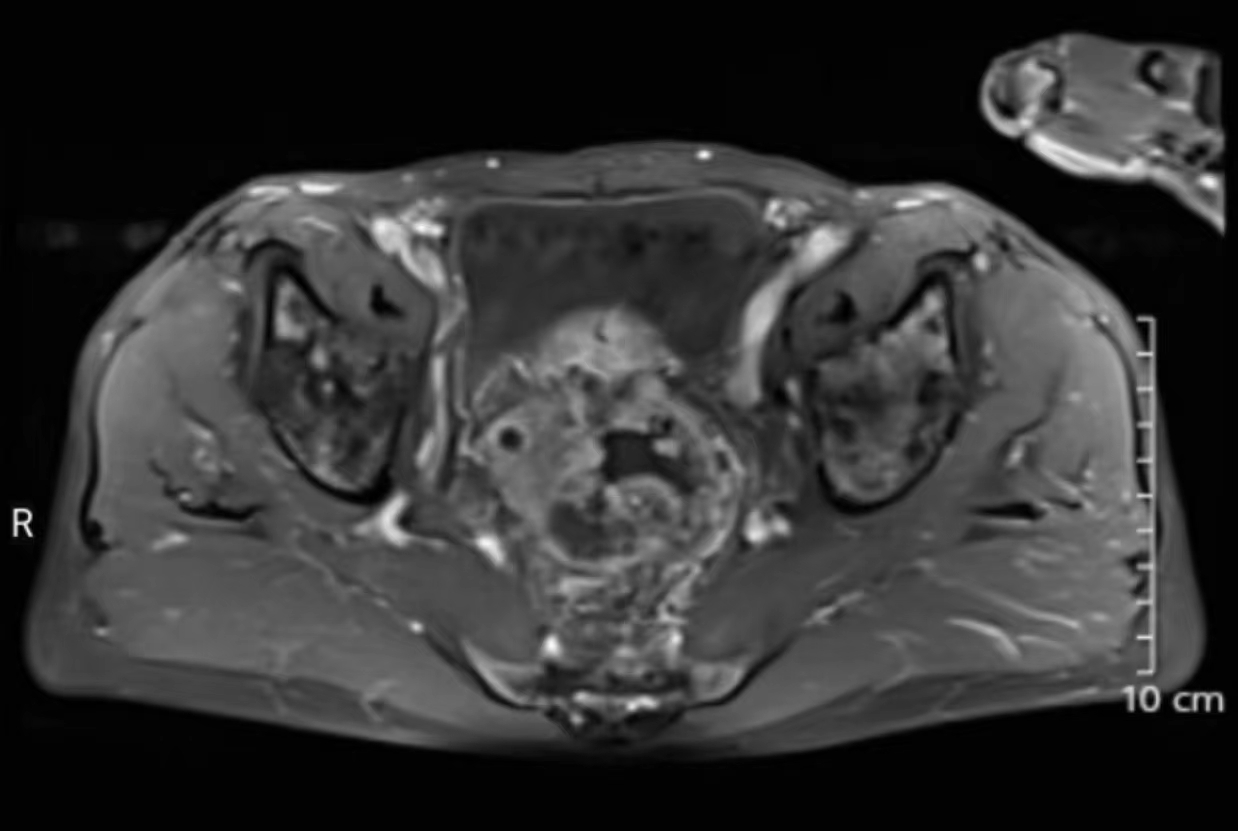

一位80岁高龄患者在一年余前于家中无明显诱因下突发腹部胀痛不适,疼痛呈阵发性,不剧,当时未予以重视。之后反复腹胀腹痛一年多,后期每日解大便数次较前增多,且每次解大便不通畅、不尽感明显。由于老年人对该疾病不敏感,一直误以为肠胃炎,没有及时就医。近期上述症状较前明显加重,遂来温州市中心医院就诊住院,查肠镜发现直肠内一较大的不规则隆起肿块,易出血,已造成肠腔狭窄梗阻,肠镜活检病理提示直肠腺癌。且进一步的腹部CT、MRI检查发现直肠肿瘤已明显侵犯右侧输尿管,导致右肾积水、右输尿管明显扩张。

MRI检查